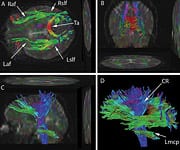

"Science now has the ability to map the entire brain, and we now know exactly where growth hormone works on mood, which pathways it uses," says Dr. Gordon. "The military is simply not prepared to go to the depths that we have in the private sector." Patients typically respond within weeks to the Millennium approach. And the responses tend to be dramatic. Gordon recalls one case in particular, of a woman who had been involved in a "T-bone" car crash - a notoriously deadly situation in which the victim's vehicle is hit full-force from the side. The patient was left with multiple neurological deficits. She spoke with a stutter and needed to keep one hand on the wall as she walked in order to maintain her balance. She had substantial memory impairment as well. After a series of blood tests, Dr. Gordon began administering small doses of the hormones that were deficient in this patient's case. She soon showed encouraging progress, with diminished speech and balance impairment. Gordon recalls with obvious delight, "One day about six months later, I got a phone call from a woman who said, in a perfectly normal voice, ‘Hi, this is your patient Nancy.' I told her to stop joking and asked who it was. ‘I'm your patient, Nancy, the one with the bad stutter. I woke up this morning, and this is how I was able to speak. I just wanted to let you know.'" Nancy's case, though dramatic, is far from unique. Since that time, Dr. Gordon has treated scores of other patients with similar outcomes, which is why military veterans coming to him are in good hands: he has obtained a grant from Access Medical Laboratories in Jupiter, Florida, which currently covers the cost of testing veterans with traumatic brain injury. "They've arranged for a phlebotomy company to go to the veterans' homes and draw blood. Lab tests use a spectrum that goes way beyond typical blood tests, providing a bigger database." Any treatment starts with baseline hormone testing of testosterone, growth hormone, thyroid, and cortisol.